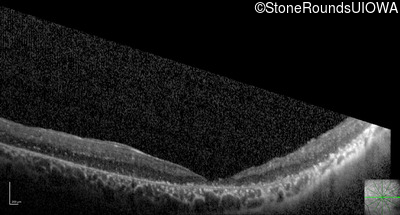

Optical Coherence Tomography - Left - Hand Motion

Exemplar / OCT Stack

OCT Stack